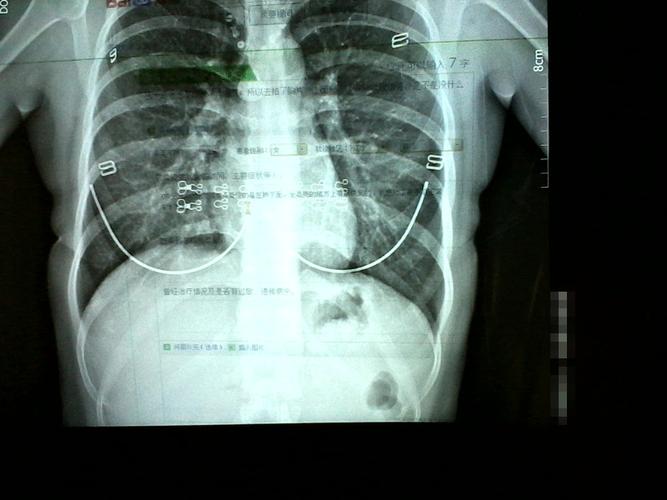

我们知道做胸片是有辐射的,如果因为这种辐射导致怀孕后胎儿受到影响会造成胎儿畸形。虽然做了胸片做可以防止辐射性反应,但是还是有必要避免做的。那么,胸片做完多久可以怀孕,怀孕前做胸片胸片可以对怀孕后胎儿造成伤害吗?